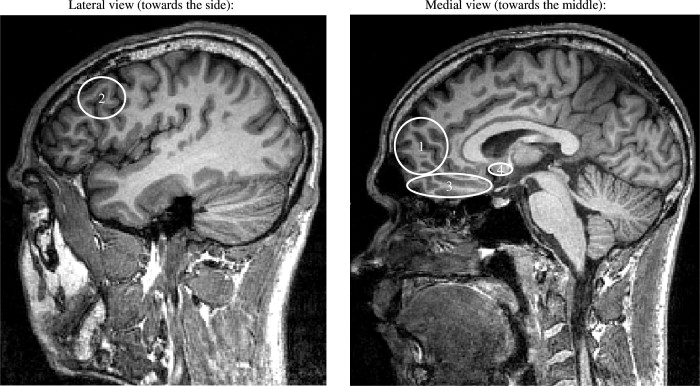

Hypotéza, ktorú predložil Damasio v knižke Descartesov omyl (2000) hovorí o možnej úlohe niektorých regiónov prefrontálneho kortexu (obrázok č. 1) v procesoch usudzovania a rozhodovania. Damasio tiež tvrdí, že oblasti spracovávajúce pocity zahrňujú okrem tradične uznávaného súhrnu mozgových štruktúr známych pod názvom limbický systém, rovnako niektoré oblasti najprednejších častí čelných lalokov, prefrontánej kôry a čo je najdôležitejšie, aj tie časti mozgu, ktoré mapujú a integrujú signály z tela.

obrázok č. 1 (Reimann a Bechara, 2010)